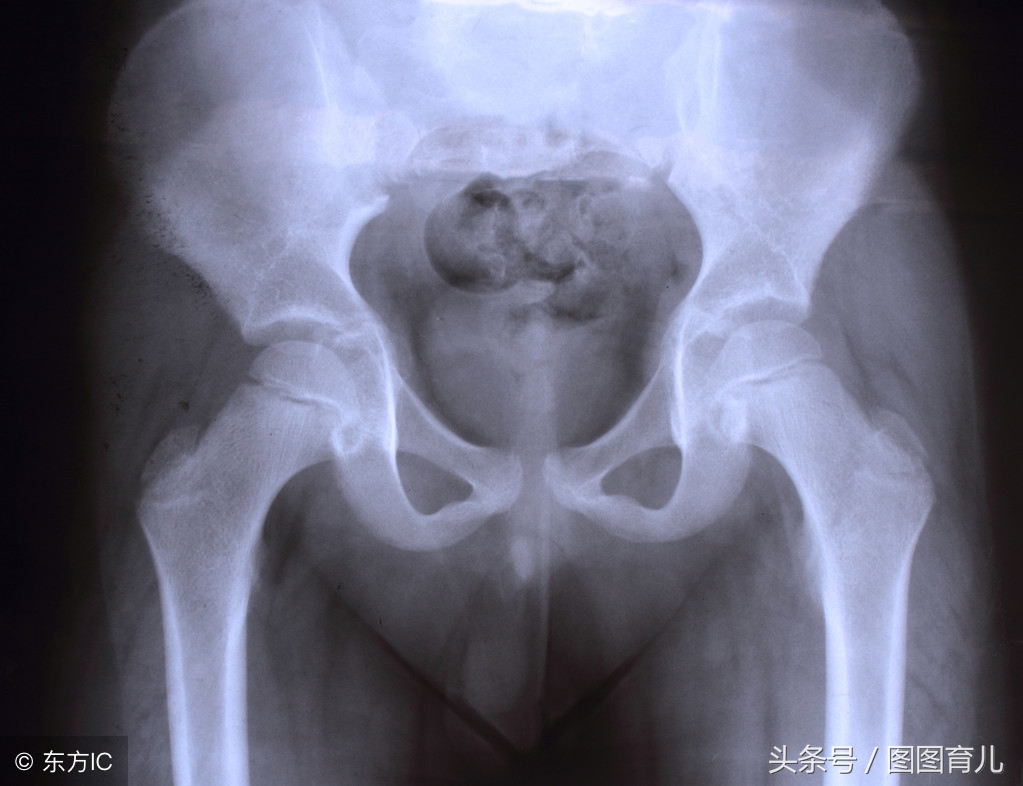

首先坐骨神经痛并不仅仅是因为身体瘦小才会被压迫,通常孕晚期的宝妈会为了迎接宝宝的到来身体自然释放一种耻骨松弛激素,根据个人的体质不同,有的孕妈妈在18周就会出现跨疼的情况,而有的则会在孕晚期才会出现,基本上每个孕妈妈都会出现类似的情况,所以不用过度担心。

随着胎儿的发育,尤其是孕晚期当胎头下降入盆时会对途经盆腔的神经进行机械性压迫,在正常情况下坐骨神经痛会在孕妈分娩后慢慢减轻并且逐渐恢复,因而并不需要进行检查治疗,可以通过非医疗的方式尽量缓解疼痛,当疼痛发生时,可以让宝爸协助尝试用热毛巾或者暖水袋进行局部热敷,一般半小时左右就可以减少疼痛,也可以在盛有温水的浴盆中浸泡,一定要把握时间,起身时要慢,注意安全。

胎儿入盆